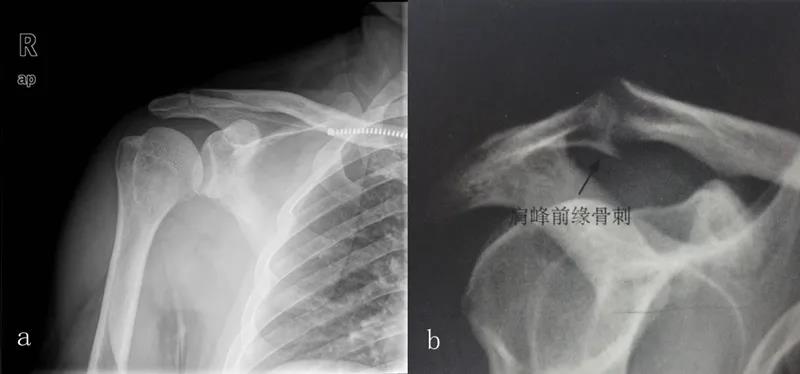

三、影像学检查1、X线检查X线检查用来评估肩峰形态,肱骨头和肩盂的关系,以及除外其他疾病。

图15 a.正常肩关节 b.肩峰撞击

图16 巨大肩袖损伤,肩峰下间隙<9mm